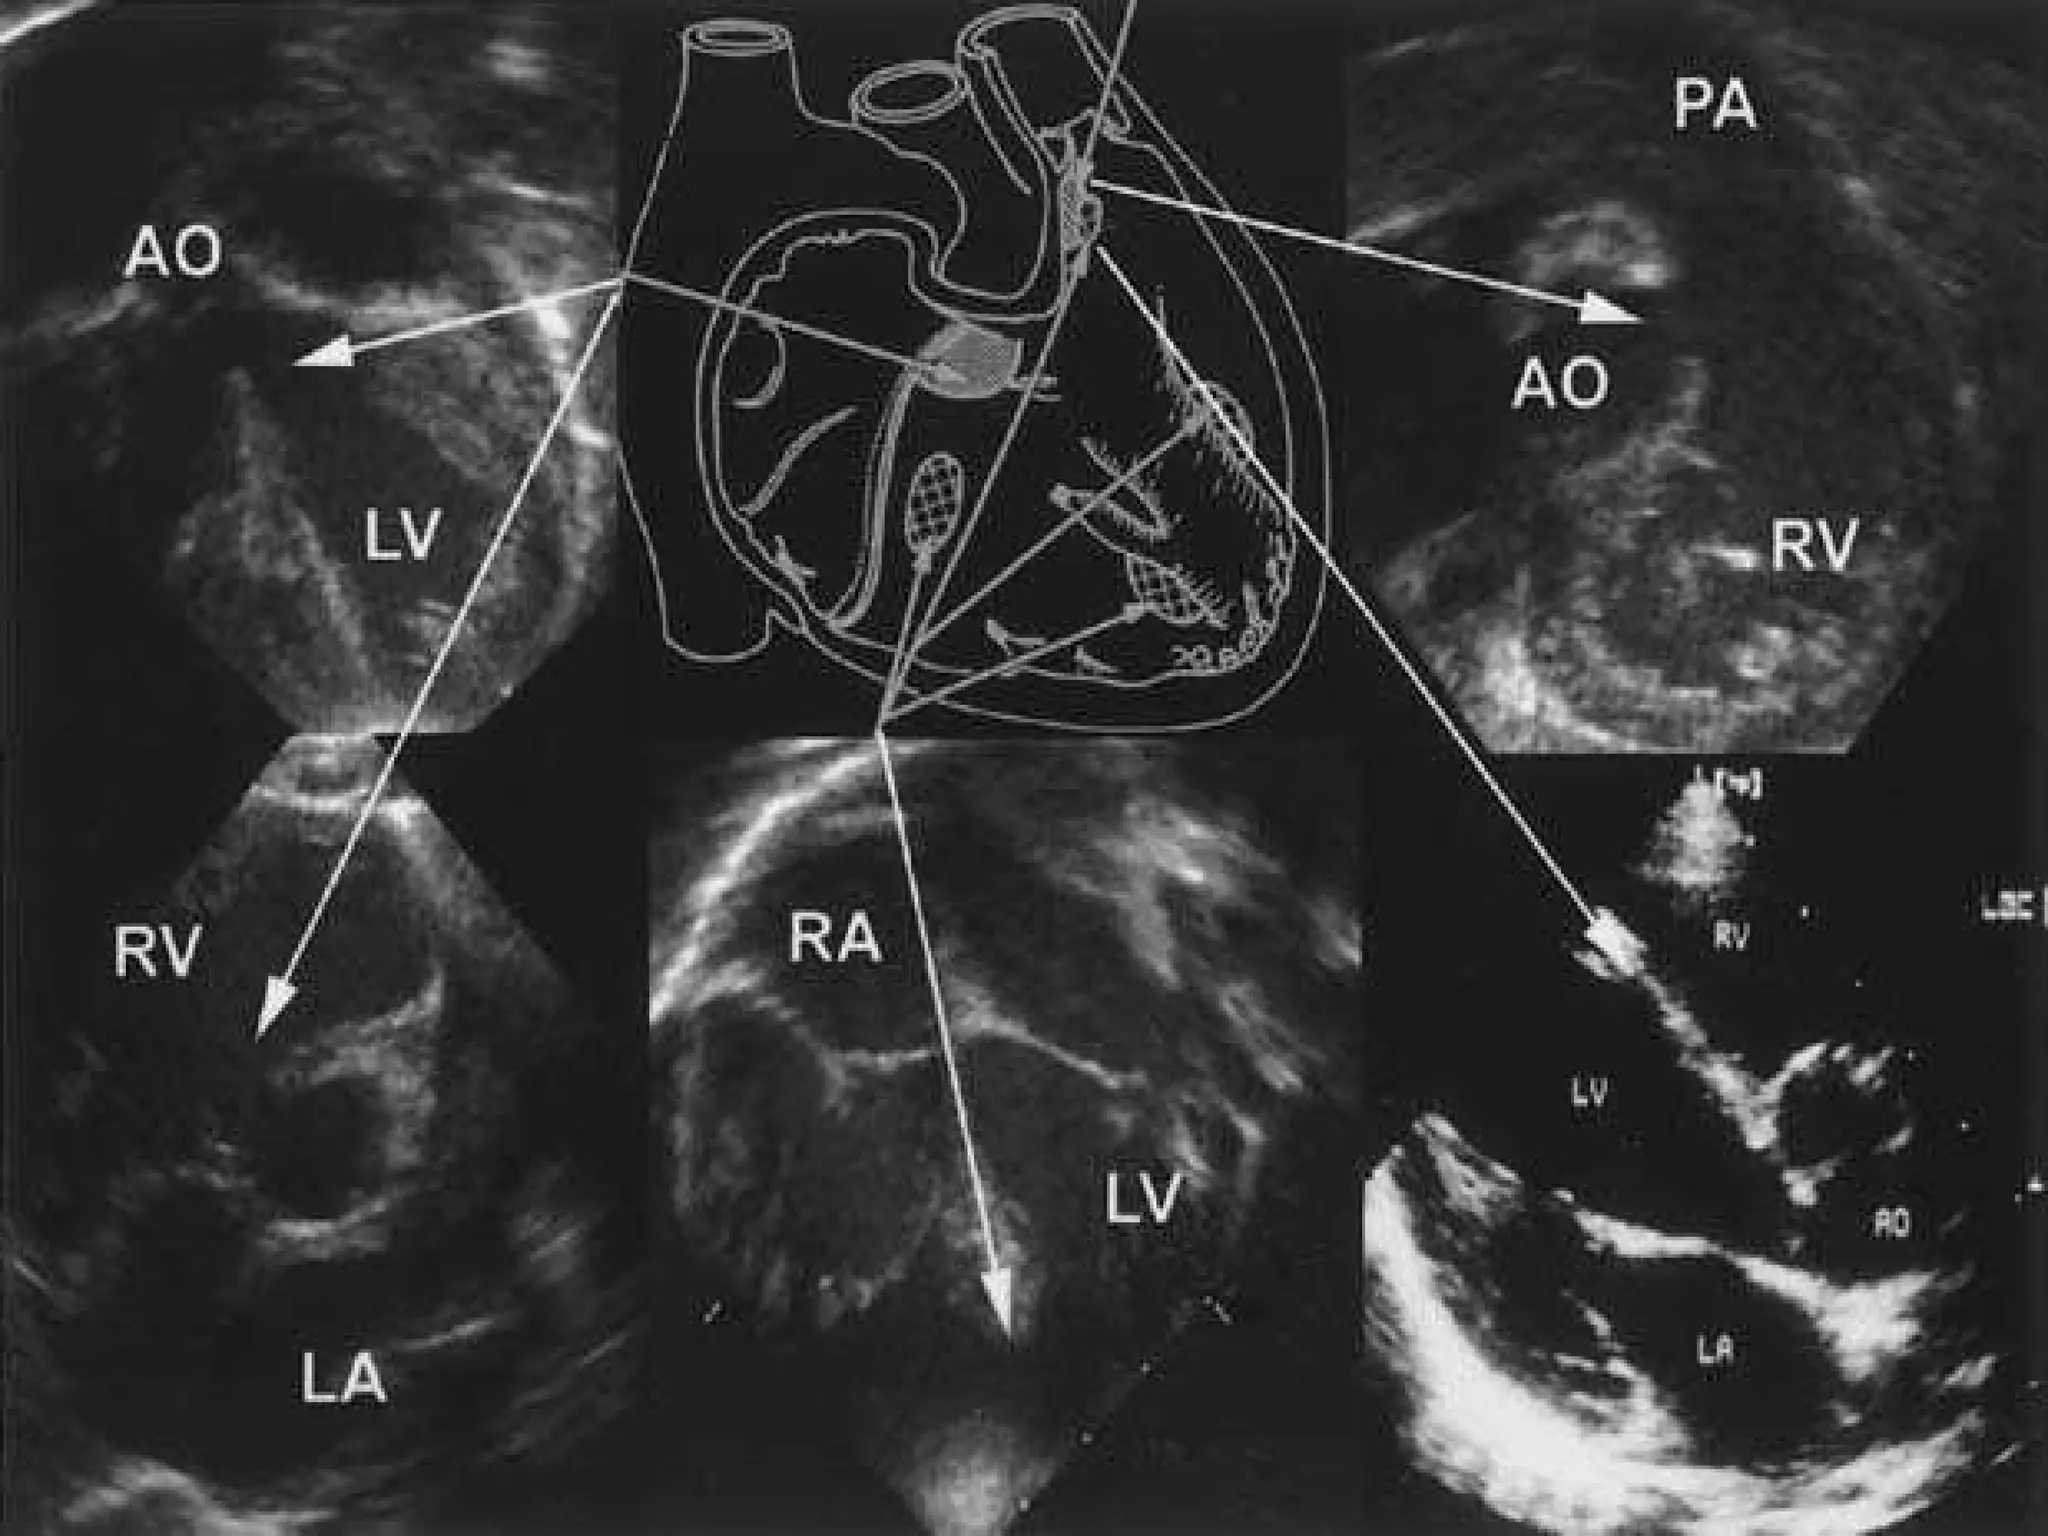

Symptoms of Atrial Septal Defect (ASD)  Many babies born with atrialseptal defects do not have signs or symptoms. In adults, signs or symptoms may not develop until age 30 or later. Your doctor may first uncover an atrialseptal defect during a regular checkup while listening to your heart using a stethoscope. Hearing a heart murmur may signal a hole in your heart.  Atrialseptal defects are often found when an ultrasound exam of the heart (echocardiogram) is done for another reason. Signs and symptoms of atrialseptal defects develop once damage occurs to the heart and lungs. Infants with larger atrialseptal defects may have poor appetites and not grow as they should. Adults and infants may have signs of heart failure or arrhythmias.

Symptoms of AtrialSeptal Defect (ASD) Many babies born with atrialseptal defects do not have signs or symptoms. In adults, signs or symptoms may not develop until age 30 or later. Your doctor may first uncover an atrialseptal defect during a regular checkup while listening to your heart using a stethoscope. Hearing a heart murmur may signal a hole in your heart. Atrialseptal defects are often found when an ultrasound exam of the heart (echocardiogram) is done for another reason. Signs and symptoms of atrialseptal defects develop once damage occurs to the heart and lungs. Infants with larger atrialseptal defects may have poor appetites and not grow as they should. Adults and infants may have signs of heart failure or arrhythmias.